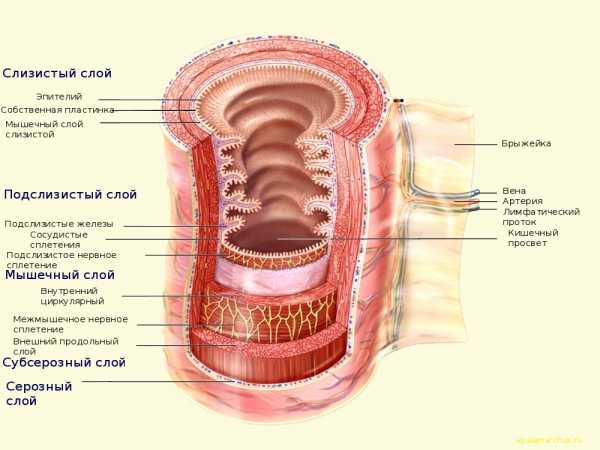

Особенности строения толстой кишки |

Общие характеристики

Толстый кишечник в брюшной полости формирует как бы «рамку» вокруг петель тонкого кишечника. Толстая кишка является конечным отделом пищеварительной системы и отвечает за поглощение солей (в основном — соли натрия) и воды. Содержит большое количество микроорганизмов как по общему числу, так и разнообразию. Длина толстого кишечника составляет около 150 см

Толстый кишечник в брюшной полости формирует как бы «рамку» вокруг петель тонкого кишечника. Толстая кишка является конечным отделом пищеварительной системы и отвечает за поглощение солей (в основном — соли натрия) и воды. Содержит большое количество микроорганизмов как по общему числу, так и разнообразию. Длина толстого кишечника составляет около 150 см

Тонкий кишечник заканчивается илеоцекальным клапаном или Баугиниевой заслонкой, впадая в купол слепой кишки. Слепая кишка находится в правой подвздошной ямке, за которой следует восходящая, поперечная, нисходящая и сигмовидная кишка. Сигмовидная кишка переходит в прямую, заканчивающуюся анальным отверстием. Ободочной называют весь толстый кишечник, за исключением прямой кишки и анального канала. Прямая кишка имеет ряд особенностей как по анатомии, так и по функции и лучше ее описать отдельно.

Поперечная ободочная кишка четко ограничена левым и правым изгибом (селезеночным и печеночным углами соответственно). Вообще, на операции определить отделы толстого кишечника очень сложно, так как по размеру они могут не отличаться. А вот от тонкой толстая кишка отличается заметно. Нужно просто знать ее анатомические особенности.

Анатомические признаки толстого кишечника

Гаустры

Гаустры толстой кишки являются характерными для нее образованиями, так сказать, ее «визитная карточка». Представляют собой характерные сферические мешочки, ограниченные друг от друга полулунными складками, хорошо видимыми изнутри кишки. И хотя гаустры есть следствие сокращения гладкой мускулатуры (на трупах в секционной они не так четко определяются), они хорошо идентифицируются при рентгенографии и хирургических вмешательствах.

Тении (ленты)

Структура кишечной стенки толстой кишки (в отличие от тонкой) — не имеет полного внешнего продольного слоя по всей окружности стенки. Наружный мышечный слой сконцентрирован в три продольные ленты — тении, хорошо определяемые невооруженным глазом. В толстом кишечнике выделяют три таких:

— Tenia mesocolica (брыжеечная лента)

— Tenia omentalis (сальниковая лента)

— Tenia libera (свободная лента)

Эти мышечные полоски непрерывны как в восходящем, так и нисходящем отделе кишки. В области купола слепой кишки они встречаются, четко «указывая» на червеобразный отросток, что может облегчить его поиск. Идем по кишке и ищем место схождения мышечных лент. Однако лент нет ни в аппендиксе, ни в прямой кишке. А в сигмовидной кишке есть только две ленты.

Толстокишечные придатки (processus epiploicae, или жировые подвески)

Представляют собой небольшие выпуклости толстой кишки, стенка которых состоит из серозного и субсерозного слоя, заполненные жировой тканью. Для хирурга важно, что в них содержатся терминальные ветви брыжеечных артерий и их хирургического удаления следует избегать.

Гистологическое строение толстой кишки

Кишечник как орган, если представить максимально просто, представляет собой полую гибкую трубку, причем многослойную. Внутренний, слизистый слой обеспечивает всасывание питательных веществ и воды, а также обеспечивает иммунный барьер от обитающей в кишечном содержимом богатой микрофлоры. Под этим слоем располагается подслизистый слой, обеспечивающий прочность кишечной стенки. Мышечные слои обеспечивают перистальтику, а также (в основном, в толстой кишке) — перемешивание кишечного содержимого. Снаружи нужна гладкая поверхность, не так ли? Минимум трения между подвижными кишечными петлями обеспечивает брюшина — гладкая серозная оболочка. Вообще, как для тонкого, так и для толстого кишечника характерен одинаковый состав слоев клеточной стенки. То есть слои те же, но у толстого кишечника есть свои особенности:

Вообще, как для тонкого, так и для толстого кишечника характерен одинаковый состав слоев клеточной стенки. То есть слои те же, но у толстого кишечника есть свои особенности:

— слизистая толстой кишки имеет гладкую поверхность (нет кишечных ворсинок)

— внешний гладкий мышечный слой собран в ленты — тении

— имеются различия в клеточной структуре эпителия

— складчатость стенки формируется за счет всех слоев стенки (в отличие от ворсин тонкой кишки).

Гистологические слои толстой кишки содержат:

— слизистая оболочка (mucosa)

— подслизистый слой (tela submucosa)

— мышечный слой (tela muscularis propria)

— субсерозный слой (tela subserosa)

— серозная оболочка, или брюшина (tunica serosa)

Слизистый слой толстой кишки. Это внутренний слой, содержащий большое количество крипт (крипты Либеркюна). Это углубления поверхности, в которых имеется большое количество желез. Эти железы намного лучше развиты, чем в тонком кишечнике. Клеточный состав представлен эпителиальными клетками, которые обеспечивают всасывание натрия и воды, бокаловидными клетками, вырабатывающими слизь (в качестве смазки), а также стволовыми клетками в глубине крипт, которые постоянно делятся и восстанавливают кишечный эпителий. Встречаются также эндокринные (энтерохромаффинные) клетки, синтезирующие гормоны. Все это выполняет основные задачи: забрать из кишечного содержимого излишки воды и минеральные вещества, обеспечить надежный барьер от микробов. К тому же слизь бережет саму слизистую от травматизации (ведь содержимое становится все плотнее).